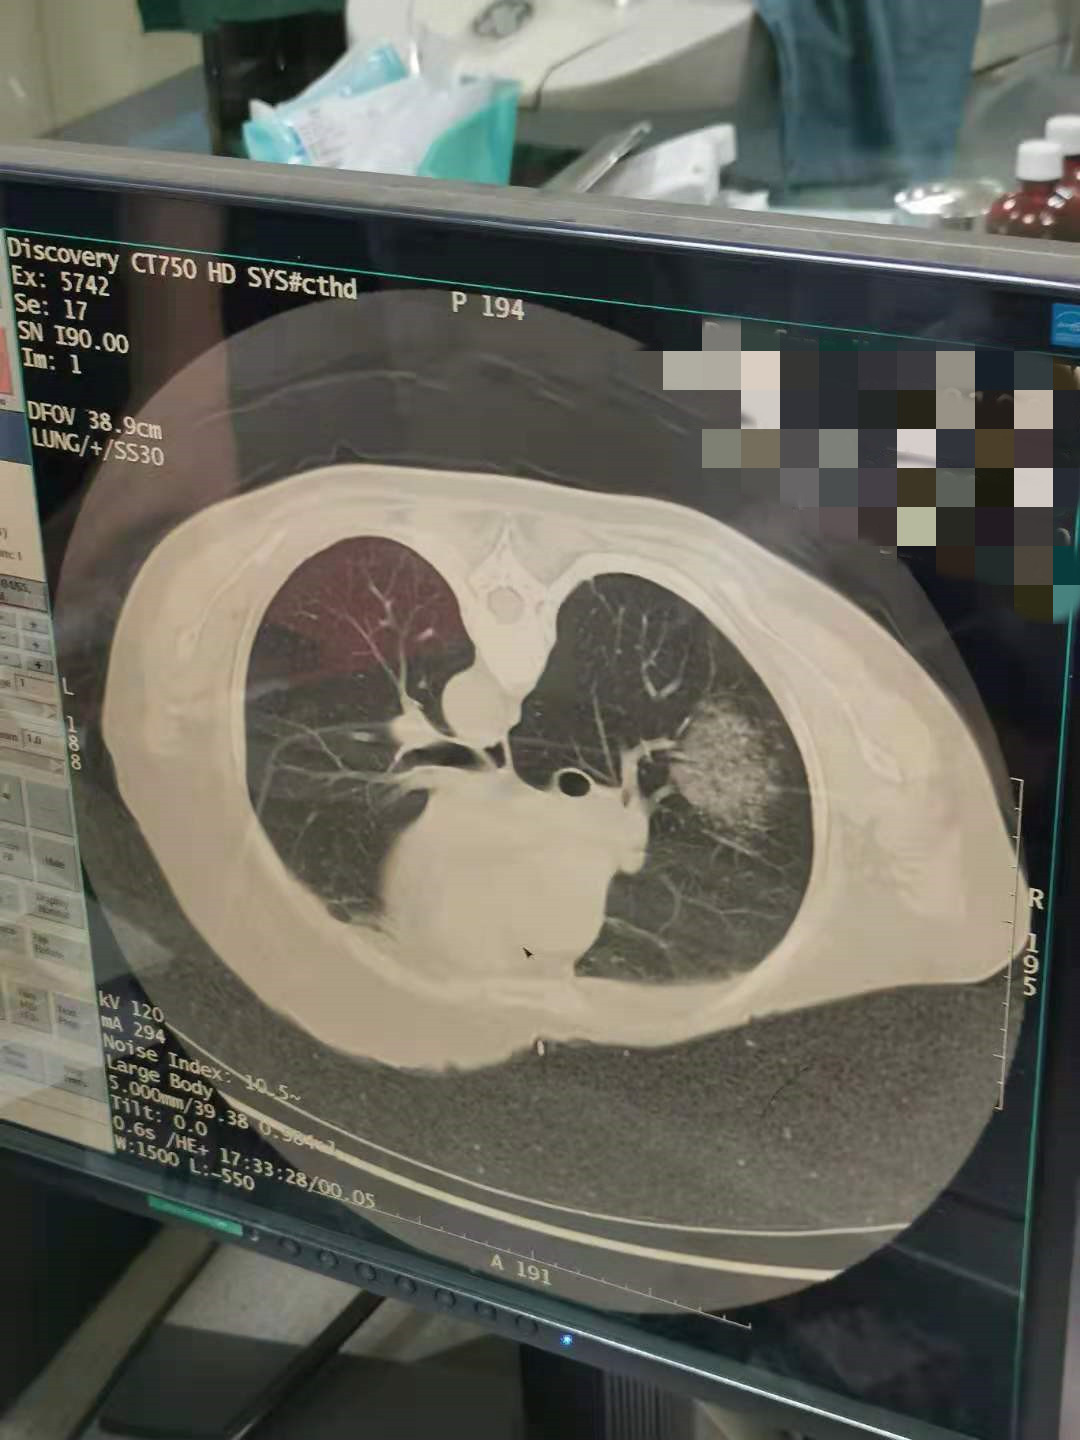

2021年7月份肺部氩氦刀手术

发布人:美国氩氦刀技术官方网站    发布时间:2021/9/22 15:53:54